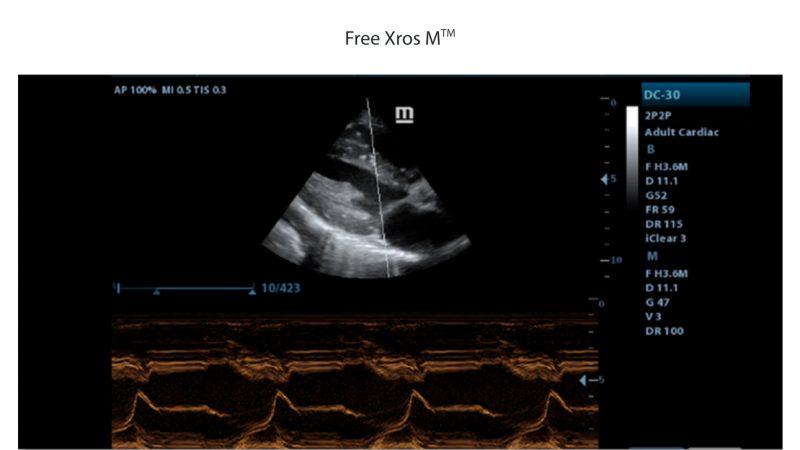

- Free Xros M, Gain precise anatomical observation by freely placing sample lines at any angle.

| Cardiac Functions | ECG module, Free Xros M, Tissue Doppler Imaging (TDI) |